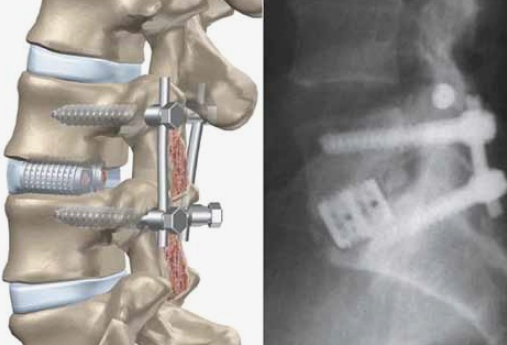

Лечение посттравматического поясничного кифоза с использованием многоуровневой остеотомии понте и заднего спондилодеза: клинический опыт 20.03.2026